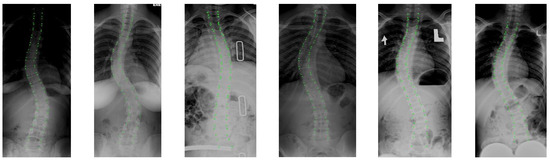

We employ a public dataset [35] for the experimental evaluation, which was collected from the London Health Sciences Center in Canada that consists of 609 coronal spinal X-ray images with sizes ranging from 359 × 973 to 1386 × 2678. To ensure the deep learning framework’s effectiveness, we scale all images to a uniform size of 512 × 1536. Since the cervical vertebrae are rarely involved in spinal deformity, 12 thoracic and 5 lumbar vertebrae for each X-ray image are annotated by two professional radiologists. Each vertebra is labeled by four landmarks with reference to four corners, resulting in 68 points per spine image, which is also considered as the ground truth (GT) of vertebrae segmentation. With the landmarks, the Cobb angles can be further calculated. After the Cobb angle of each spine is determined, the Lenke type of scoliosis is annotated. For experimental data, we randomly selected 80% for training, 10% for validation, and 10% for testing. Some original image samples are shown in Figure 13.

Figure 13.

The examples of original image samples.